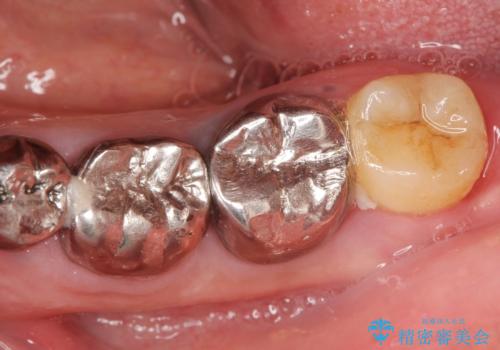

機能していない親知らずを用いて咬合を回復することができ、喜んで頂けました。

患者様のモチベーションが上がり、他の部位の治療も希望され現在治療中です。

また、プラークコントロール不良のためブラッシング指導も行っております。